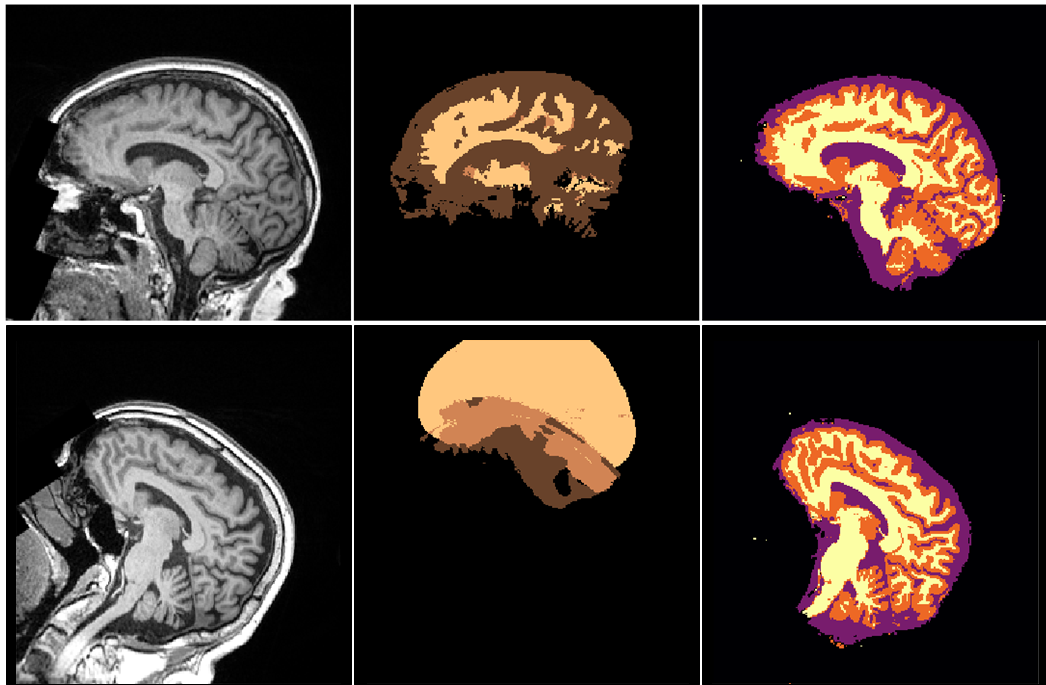

Refer to caption

Figure 1: Random exemplary UK Biobank case processed with FSL [1], SPM [2] and MALP-EM [3] after pre-processing according to [7]: (from top left to bottom right): Raw T1w MR image, FSL First, MALP-EM, SPM tissue, FSL fast, MALP-EM tissue segmentations.

Further, traditional pipelines require extensive pre-processing of the input images to improve the initial conditions for the subsequent segmentation method. This can include spatial normalisation via registration to an atlas (e.g. MNI152111http://www.bic.mni.mcgill.ca/ServicesAtlases/ICBM152NLin6), correction of the bias field [8] and employing brain stripping methods [9], further exacerbating the computational burden required to process a subject (c.f. running all packages to obtain the outputs shown in Fig. 1 requires several hours per scan).

Accurate and robust structural segmentation of the brain is a key component in neuroimaging research. Semantic segmentation and, thus, the identification of cortical and subcortical structures allows quantification of anatomical variation (e.g., hippocampal volume, gray matter thickness, white matter loss, etc.) and relation of brain function and connectivity to meaningful spatial locations. Well-established segmentation tools, such as FSL [1], SPM [2] and others [3], have been developed and frequently employed over the last decade. These tools exhibit different strengths and weaknesses [4, 5] and neuroscientists are left with an agony of choice knowing that different tools might introduce different biases [6] (c.f. the subcortical GM segments in Figure 1). This may negatively impact findings and weaken any drawn conclusions.